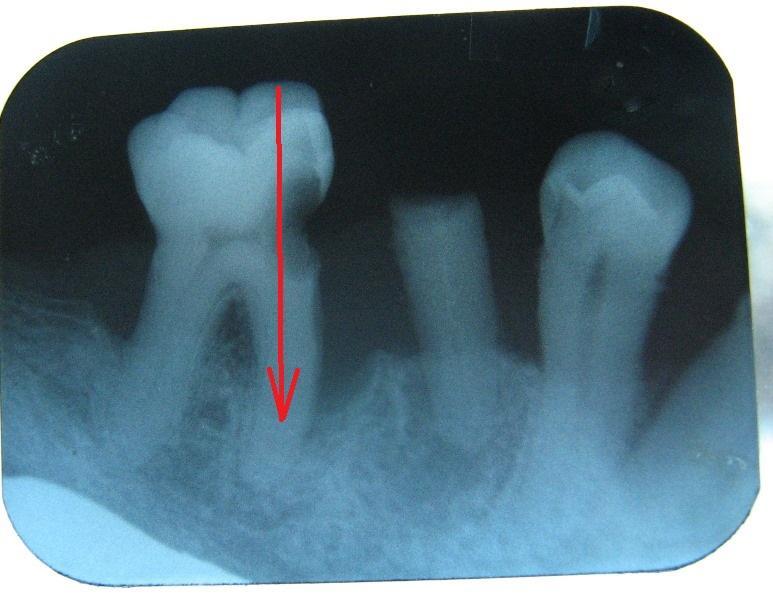

Образовался кариес у коренного зуба в не удобном месте -сбоку, местные врачи отказываются лечить мотивируя тем что зуб не лечится, направляют на удаление...попросил врача убить и удалить нерв воизбежания проблем, врач тоже отказался сказал что не сможет провести санитарию канала...странно как то...неужели сверху не льзя просверлить зуб в канал?